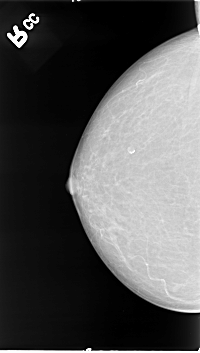

B_3066_1.LEFT_CC

LEFT_CC LINES 4632 PIXELS_PER_LINE 2200 BITS_PER_PIXEL 12 RESOLUTION 50 OVERLAY

FILE: B_3066_1.LEFT_CC.OVERLAY

TOTAL_ABNORMALITIES 1

ABNORMALITY 1

LESION_TYPE MASS SHAPE IRREGULAR MARGINS CIRCUMSCRIBED-ILL_DEFINED

ASSESSMENT 4

SUBTLETY 5

PATHOLOGY MALIGNANT

TOTAL_OUTLINES 1

BOUNDARY